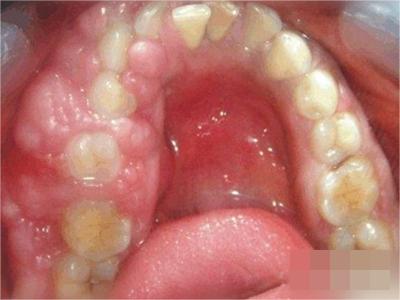

牙龈瘤是指发生在龈乳头部位的炎症反应性瘤样增生物,好发于女性,前磨牙区最为常见。牙龈瘤来源于牙周膜及牙龈的结缔组织,因其无肿瘤的生物学特征和结构,故非真性肿瘤,但切除后易复发,因此切除务必彻底,必要时拔除相关牙齿。

牙龈瘤多发于女性,以青年及中年人为常见,多发生于牙龈乳头部,位于唇、颊侧者较舌、腭侧者多,最常见的部位是前磨牙区。肿块较局限,呈圆形或椭圆形,有时呈分叶状,大小不一,直径由几毫米至数厘米。

肿块有的有蒂,如息肉状;有的无蒂,基底宽广,生长较慢,但在女性妊娠期间可能迅速增大。较大的肿块可以遮盖一部分牙及牙槽突,表面可见牙压痕,易被咬伤而发生溃疡,伴发感染。随着肿块的增长,牙槽骨壁逐渐被破坏,牙可能发生松动、移位。

局部刺激因素,包括菌斑、牙石、食物嵌塞或不良修复体的刺激,引起局部长期慢性炎症,致使牙龈结缔组织形成反应性增生物,即牙龈瘤。此外,牙龈瘤可能和内分泌有关,妇女怀孕期间容易发生牙龈瘤,而分娩后会缩小或停止生长。